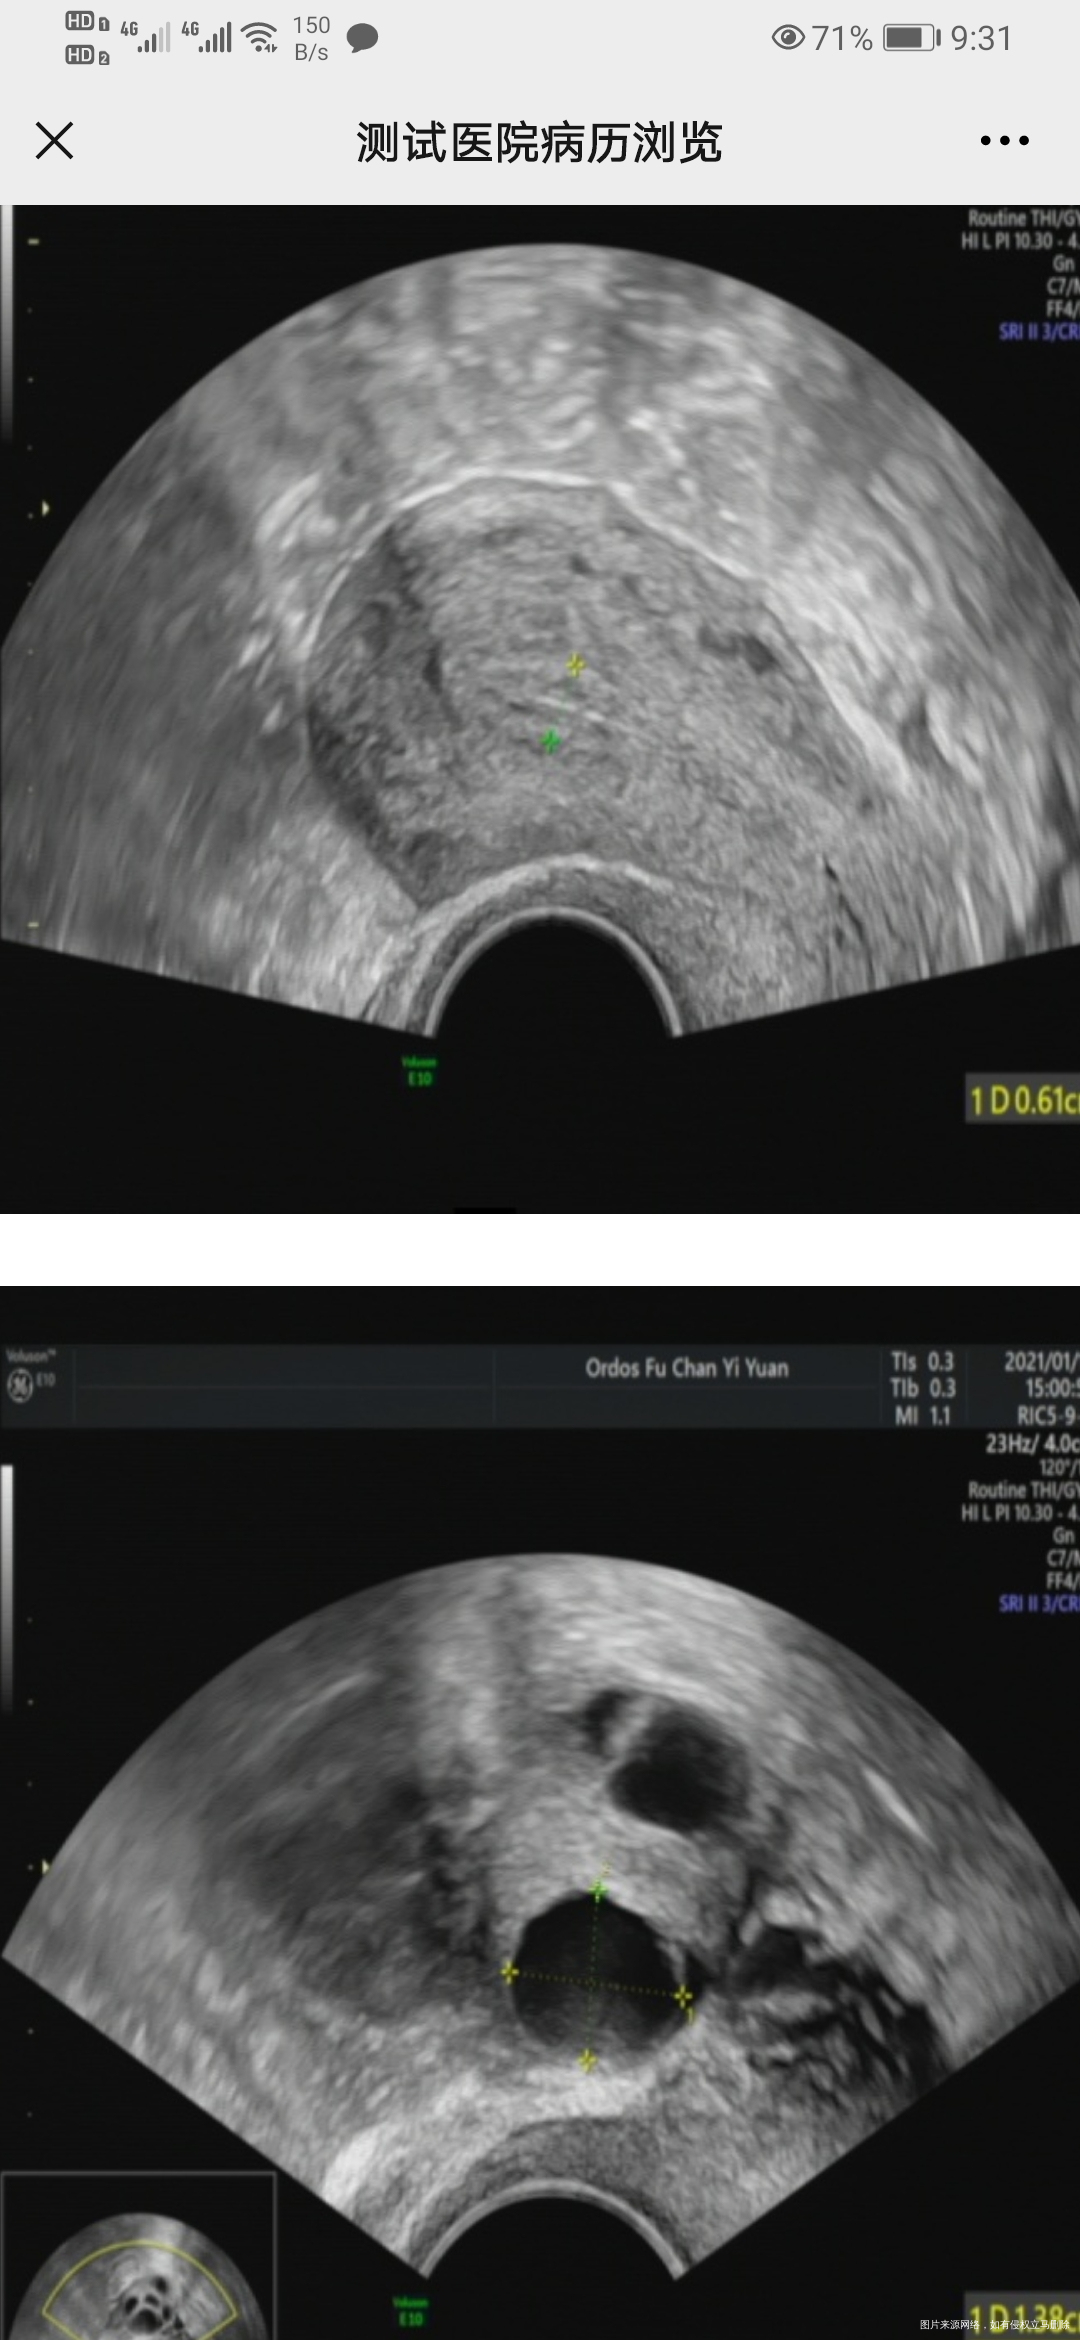

1楼彩超显示多囊卵巢,但还需要查性激素六项,根据睾酮值,LH/FSH值,及月经情况,综合判断是否多囊

4楼您好,多囊的诊断标准1.稀发排卵或无排卵。(表现为月经不规则,闭经)2.高雄激素的临床表现和/或高雄激素血症。(表现为多毛痤疮等)3.超声表现为多囊卵巢(一侧或双侧卵巢有12个以上直径为2~9mm的卵泡,和/或卵巢体积大于10ml)。上述3条中符合2条,并排除其他疾病如先天性肾上腺皮质增生、库欣综合征、分泌雄激素的肿瘤。综合以上才能判断是不是多囊。单纯超声不能直接说是,只能说是卵巢多囊样改变

2021-02-05 14:57:25 回复

陈淑萍

5楼1.稀发排卵或无排卵。是必备条件哦。